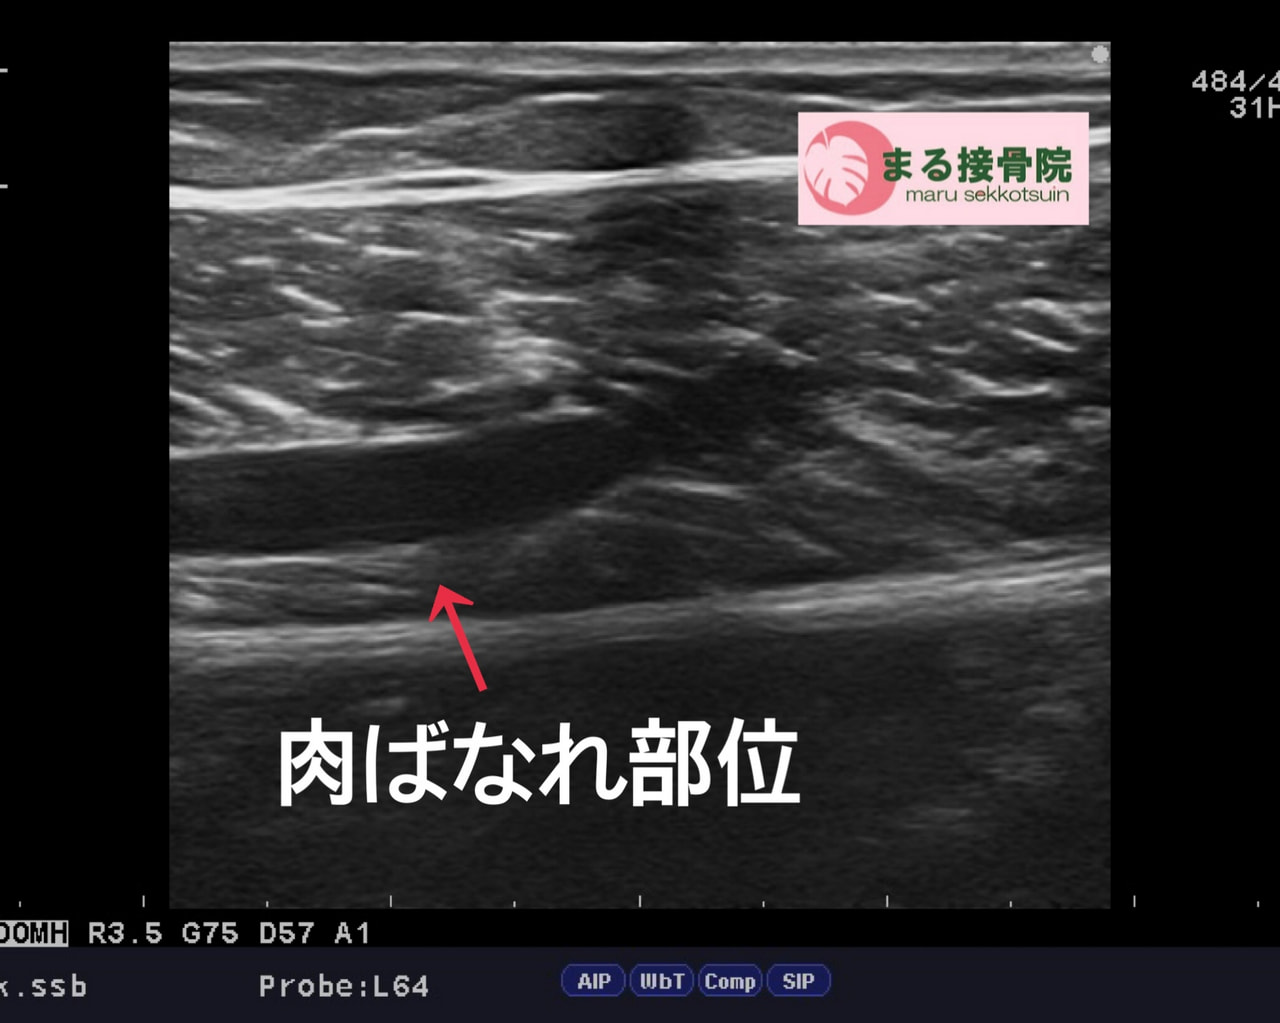

そのうえで、損傷の状態をより正確に確認するために

エコー(超音波)検査を実施しました。

エコー検査の結果、

**腓腹筋の筋線維損傷(肉離れ)**であることが確認されました。